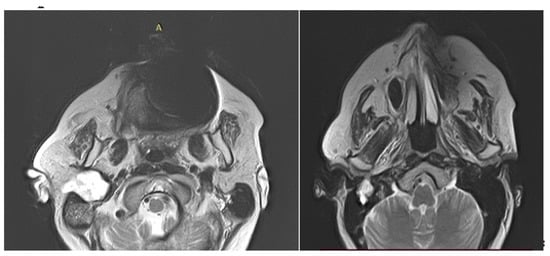

4. Imagery in Extracranial FNSs